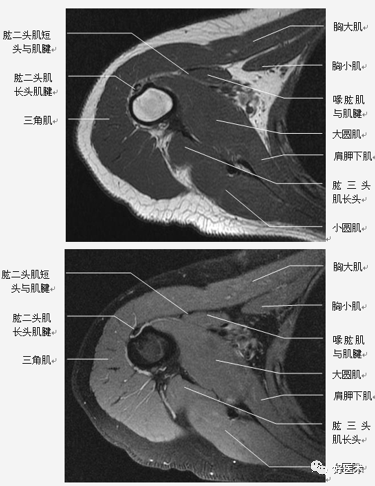

(2)肩袖

肩袖是由冈上肌、冈下肌、小圆肌和肩胛下肌的肌腱构成。前三个肌腱由上向下均止于肱骨大结节,而肩胛下肌腱止于肱骨小结节。

位于冈上肌腱与肩胛下肌腱之间的间隙称之为旋转间隙( rotator interval) 。其内有喙肱韧带、肱二头肌长头腱、上盂肱韧带和喙突。